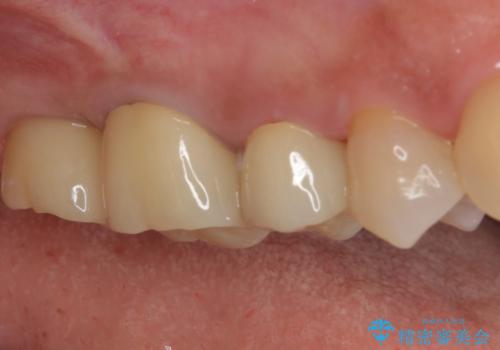

- 歯が欠損したままの奥歯のクラウンが欠けているとのことで来院された患者様です。

右上の一番奥の歯が欠損しており、その手前の歯2つを土台に連結されたクラウンが装着されていました。

不安定な咬み合わせとなっており、クラウンの表面が剥離していたため、インプラントによる欠損補綴治療を行い、手前2つの歯も一緒に補綴治療を行うこととしました。

治療中の仮歯も頻繁に壊れておりましたが、インプラントの土台が歯肉上に出てからは咬み合わせが安定し、仮歯が壊れることもなくなりました。